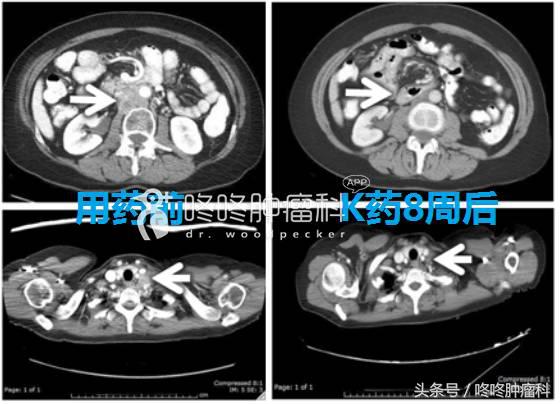

POLE突变:有效率可能更高

目前,国内外已经有POLE基因突变的子宫内膜癌、肠癌和肺癌患者使用PD-1抗体之后效果很好,比如下面这位国外的子宫内膜癌患者,用药8周之后,肿瘤明显缩小,疗效维持了至少14个月(肿瘤有POLE突变?恭喜你,中大奖了!)。